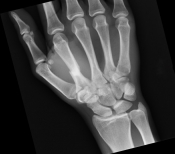

What’s the diagnosis? Gepost op 14 februari 20218 februari 2021 door netwerkvsseh What’s the diagnosis? By Dr. Becca Fieles @emdaily.cooperhealth.org Dit delen: Delen op X (Opent in een nieuw venster) X Share op Facebook (Opent in een nieuw venster) Facebook Delen op LinkedIn (Opent in een nieuw venster) LinkedIn E-mail een link naar een vriend (Opent in een nieuw venster) E-mail Afdrukken (Opent in een nieuw venster) Print Vind-ik-leuk Aan het laden... Gerelateerd